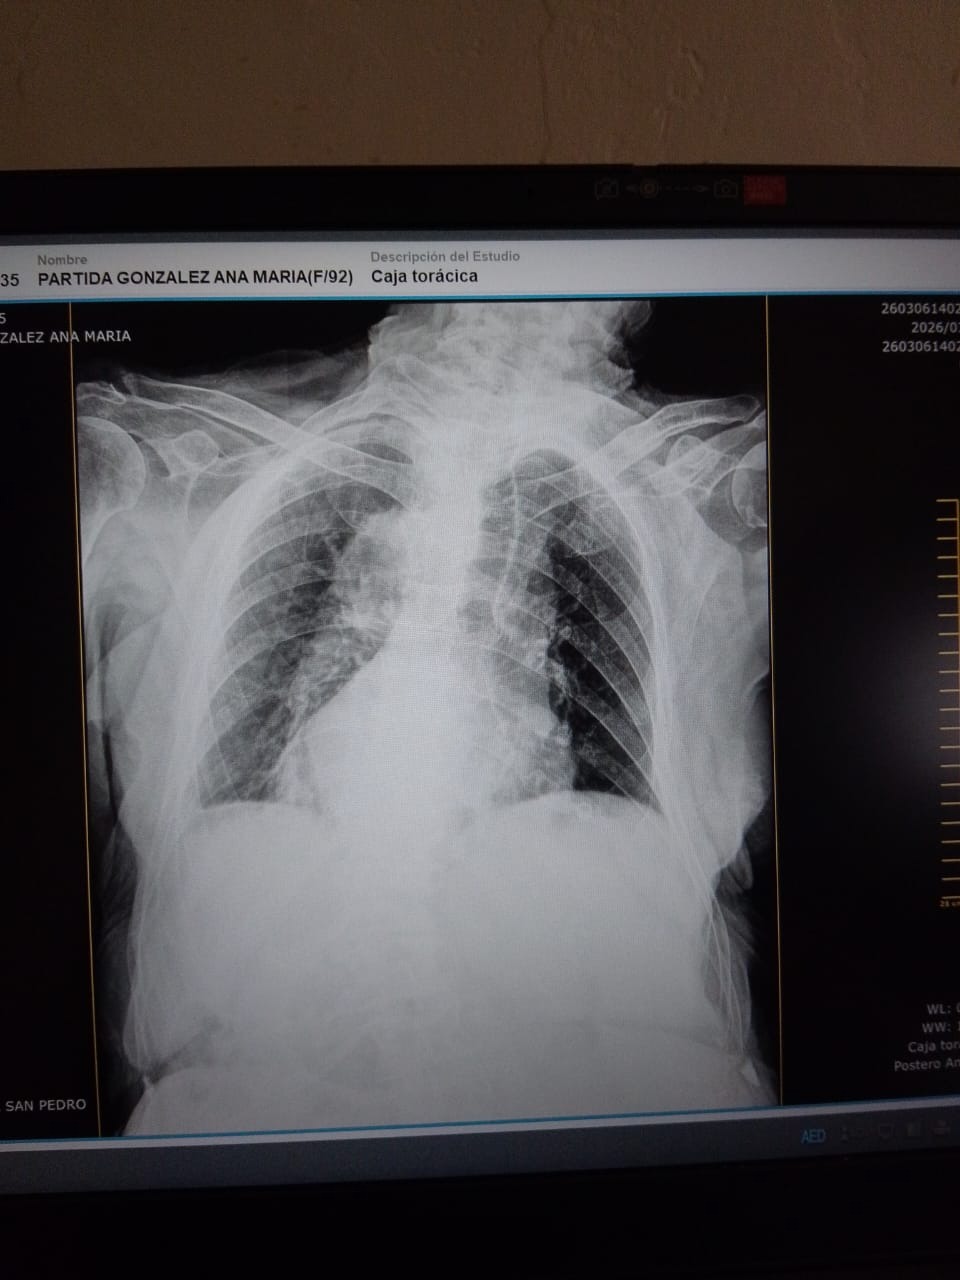

A lo largo de mi enfermedad he sufrido diferentes accidentes por las caidas, he estado en quierofano varias ocaciones. Hace unos dias mi salud se deterrioro mis pulmones estan dañados, los Doctores me dignosticaron Efisema pulmonar, y neumonia. Hoy estoy conectada a un tanque de oxígeno 24 horas del día, Es difícil cubrir los gastos de mi enfermedad entre medicamentos, pañales, y cuidados.